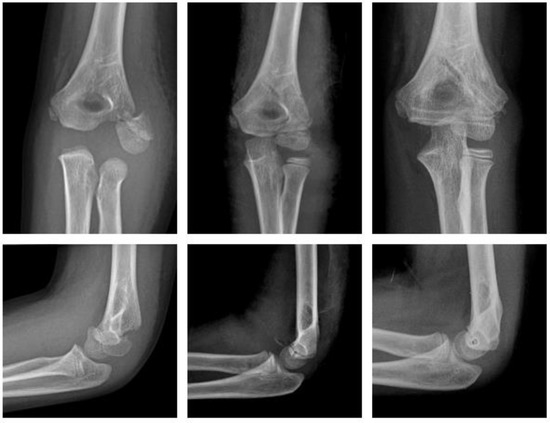

2.4.3. Fracture of the Lateral Condyle